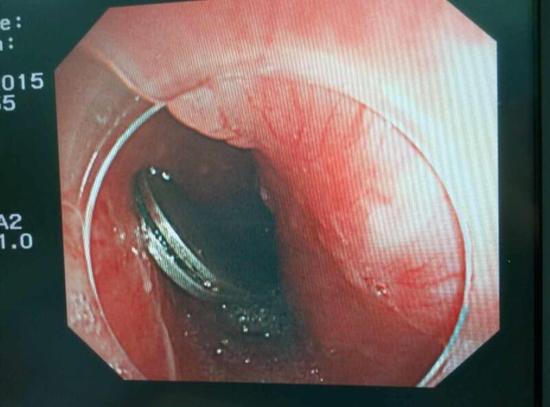

手術中,范醫(yī)生通過胃鏡準確發(fā)現(xiàn)了胃里的鑷子。但讓他驚訝的是,在華先生胃底竟然還躺著三個被腐蝕了的打火機,打火機的金屬部件都已經(jīng)不見了。

隨后,范醫(yī)生先用圈套器套取出了長10厘米的鑷子,再一個一個地取出了打火機。整個取出過程小心謹慎而又一氣呵成,只用了不到10分鐘。